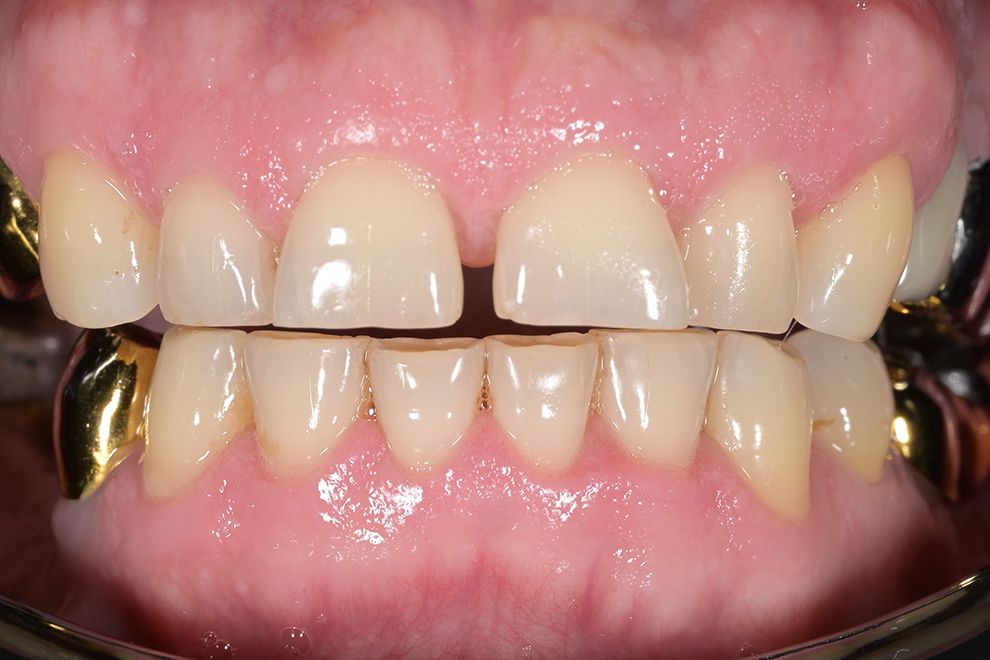

до и после